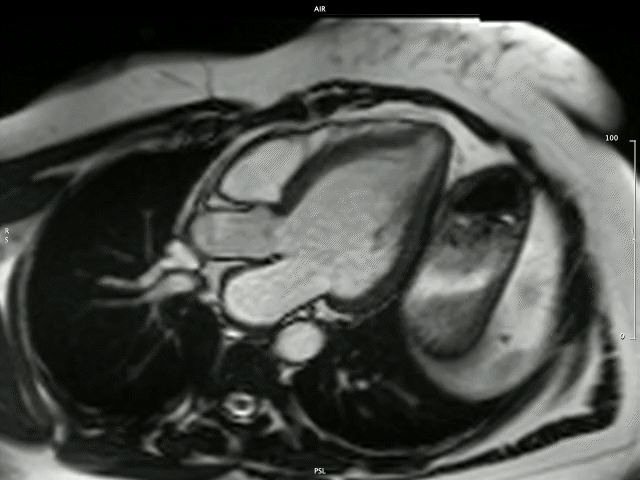

The Division is known locally and internationally as a centre of imaging excellence within both the clinical and research setting. The imaging expertise unit stretches across modalities, including 2D and 3D echocardiography, and state-of-the-art cardiovascular magnetic resonance (CMR) imaging that includes multiparametric mapping demonstrated below.

Takotsubo cardiomyopathy

Image by: Dr P-P Robbertse